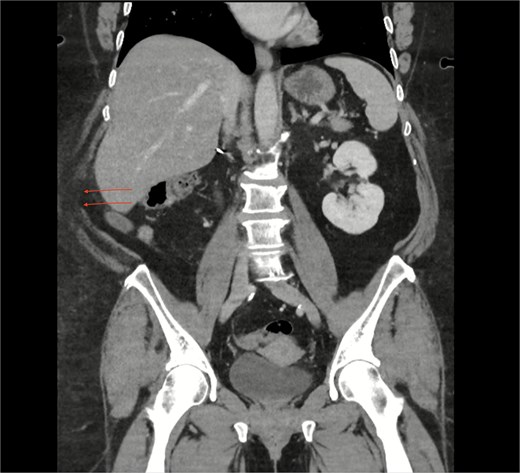

An urgent computed tomography (CT)-abdomen/pelvis highlighted an inflamed appendix extending into a small hernial defect in the right posterolateral abdominal wall (Figs 1–3). Thus, diagnosing retroperitoneal acute appendicitis within a right nephrectomy incisional hernia. The patient was started on intravenous Ceftriaxone and Metronidazole prior to deciding upon an open appendicectomy and repair of the incisional hernia using biological mesh.

CT coronal section highlighting notable right posterolateral abdominal wall defect (arrows).